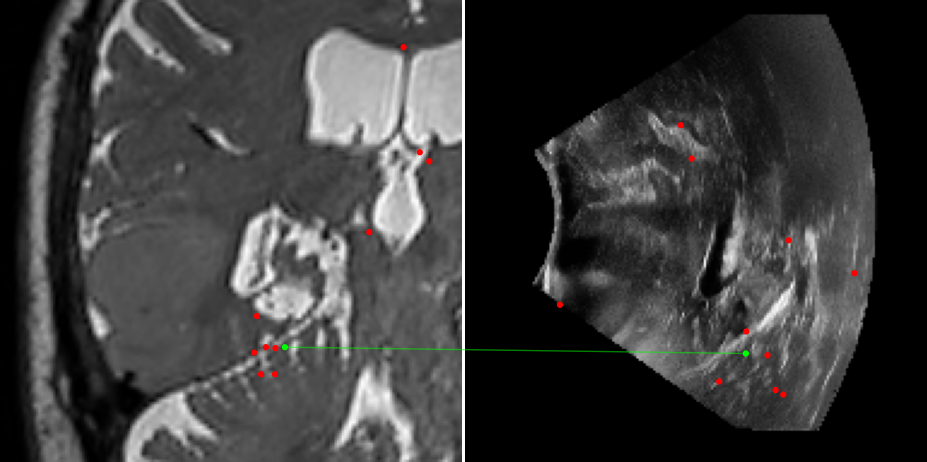

Figure 3: Examples of matching on three cases, one per column (MR on left and US on right). From top to bottom: SIFT+Cosine, MIND+Cosine, SP+Cosine, SP+LG, Ours+LG, Ours+Cosine. Correct matches recovered by each method are shown in green lines and mismatched are shown with a red dot.

To evaluate the performance of our model against existing image methods, we compared it to three approaches: SIFT [16], which remains the standard for keypoints matching, SuperPoint (SP) [3] built using a self-supervised learning approach and MIND [10], a modality-invariant descriptor for medical imaging, that although not designed for 1-to-1 keypoint matching, is extensively used for multimodal medical image registration through grid regularizing. We use SIFT and SP as keypoints detectors and descriptors, while we combine MIND with SP keypoints since it only provides a descriptor. We match these descriptors using both Cosine similarity and the deep neural network LightGlue (LG) [15] when possible (SP and Ours). Results reported in Table 2 and shown in Fig. 3 show that our approach outperforms these methods in terms of matching score, precision, and number of matched points. We only report results on three cases for readability reasons. Associating our descriptor with Cosine and LG reached similar performance depending on the metric.